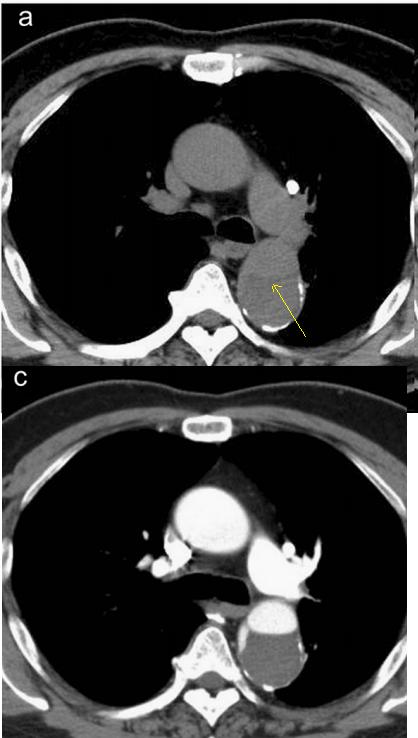

增强CT一看,主动脉夹层,密度相对高的是流动的血液!

下图的胸部CT平扫,基本上大约肯定可以看到一条线样阴影,将主动脉一分为二!

增强CT一看,主动脉裂开了!

下面的CT平扫,隐隐约约基本肯定看到主动脉夹层了!

不行,你再看看,越看越像!

增强CT一看,主动脉的确裂开了!

下面这个CT平扫,

这里有大问题!

很可惜,这个不是问题,很多CT平扫都有这种线样阴影!

下图是:大约肯定有血管内线样阴影!

下图是:隐隐约约不肯定有血管内线样阴影!